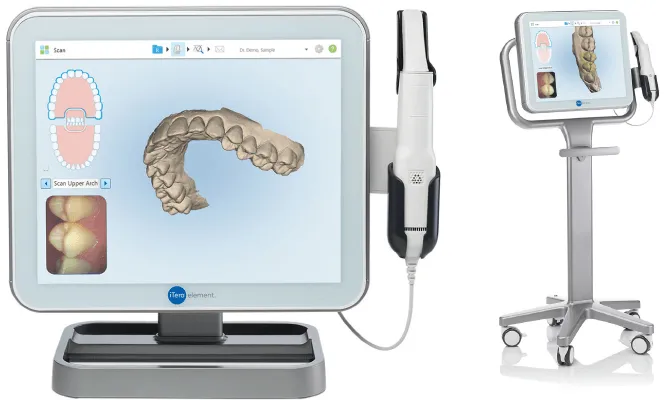

Trong bối cảnh nha khoa số hóa ngày càng phát triển, máy quét iTero Lumina™ ra đời như một bước tiến vượt bậc, mang đến giải pháp

Ngày 03/01/2025, tại cơ sở Nha Khoa DrGreen – HDS 11 Vinhomes Marina, Cầu Rào 2, Vĩnh Niệm, Lê Chân, Hải Phòng, lễ bàn giao Itero Lumina